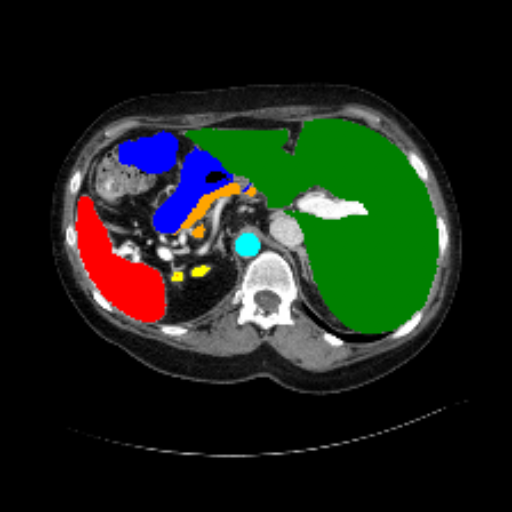

Figure 3 presents a qualitative comparison of segmentation performance on examples from the Synapse, BTCV, ACDC, and ISIC17 datasets. The first two examples (from Synapse) highlight variations in segmentation performance among U-Net, TransUnet, Mamba-Unet, and Swin-Unet. While Swin-Unet performs well in the first example, its performance decreases in the second example, particularly in segmenting the organ highlighted in blue. Additionally, it misclassifies background regions as the class highlighted in orange. In contrast, our approach demonstrates high robustness in segmenting all classes accurately and aligning well with the ground truth masks.

Across BTCV, ACDC, and ISIC17, the comparison methods exhibit varying performance depending on the task and class. For instance, Mamba-Unet struggles to segment multiple organs in BTCV, even misclassifying certain classes as others. In the ACDC dataset, both TransUnet and Mamba-Unet perform poorly in segmenting the three classes. In the last column (ISIC17), Swin-Unet oversegments the skin lesion compared to the ground truth. Unlike the comparison models, our approach consistently delivers effective segmentation across different tasks and datasets.

These qualitative findings further reinforce the quantitative results presented in the experimental section, demonstrating the effectiveness of our MambaCAFU model in handling binary and multi-class segmentation across diverse medical imaging modalities and tasks.

Slice GT Unet TransUnet Mamba-Unet Swin-UMamba MambaCAFU-V1

Figure 3: Visual comparison of segmentation examples from Synapse (first two examples), BTCV (3-4 examples), ACDC (5th example) and ISIC17 (last example). Columns: input slice, ground truth, Unet, TransUnet, Mamba-Unet, Swin-UMamba, and MambaCAFU-V1.